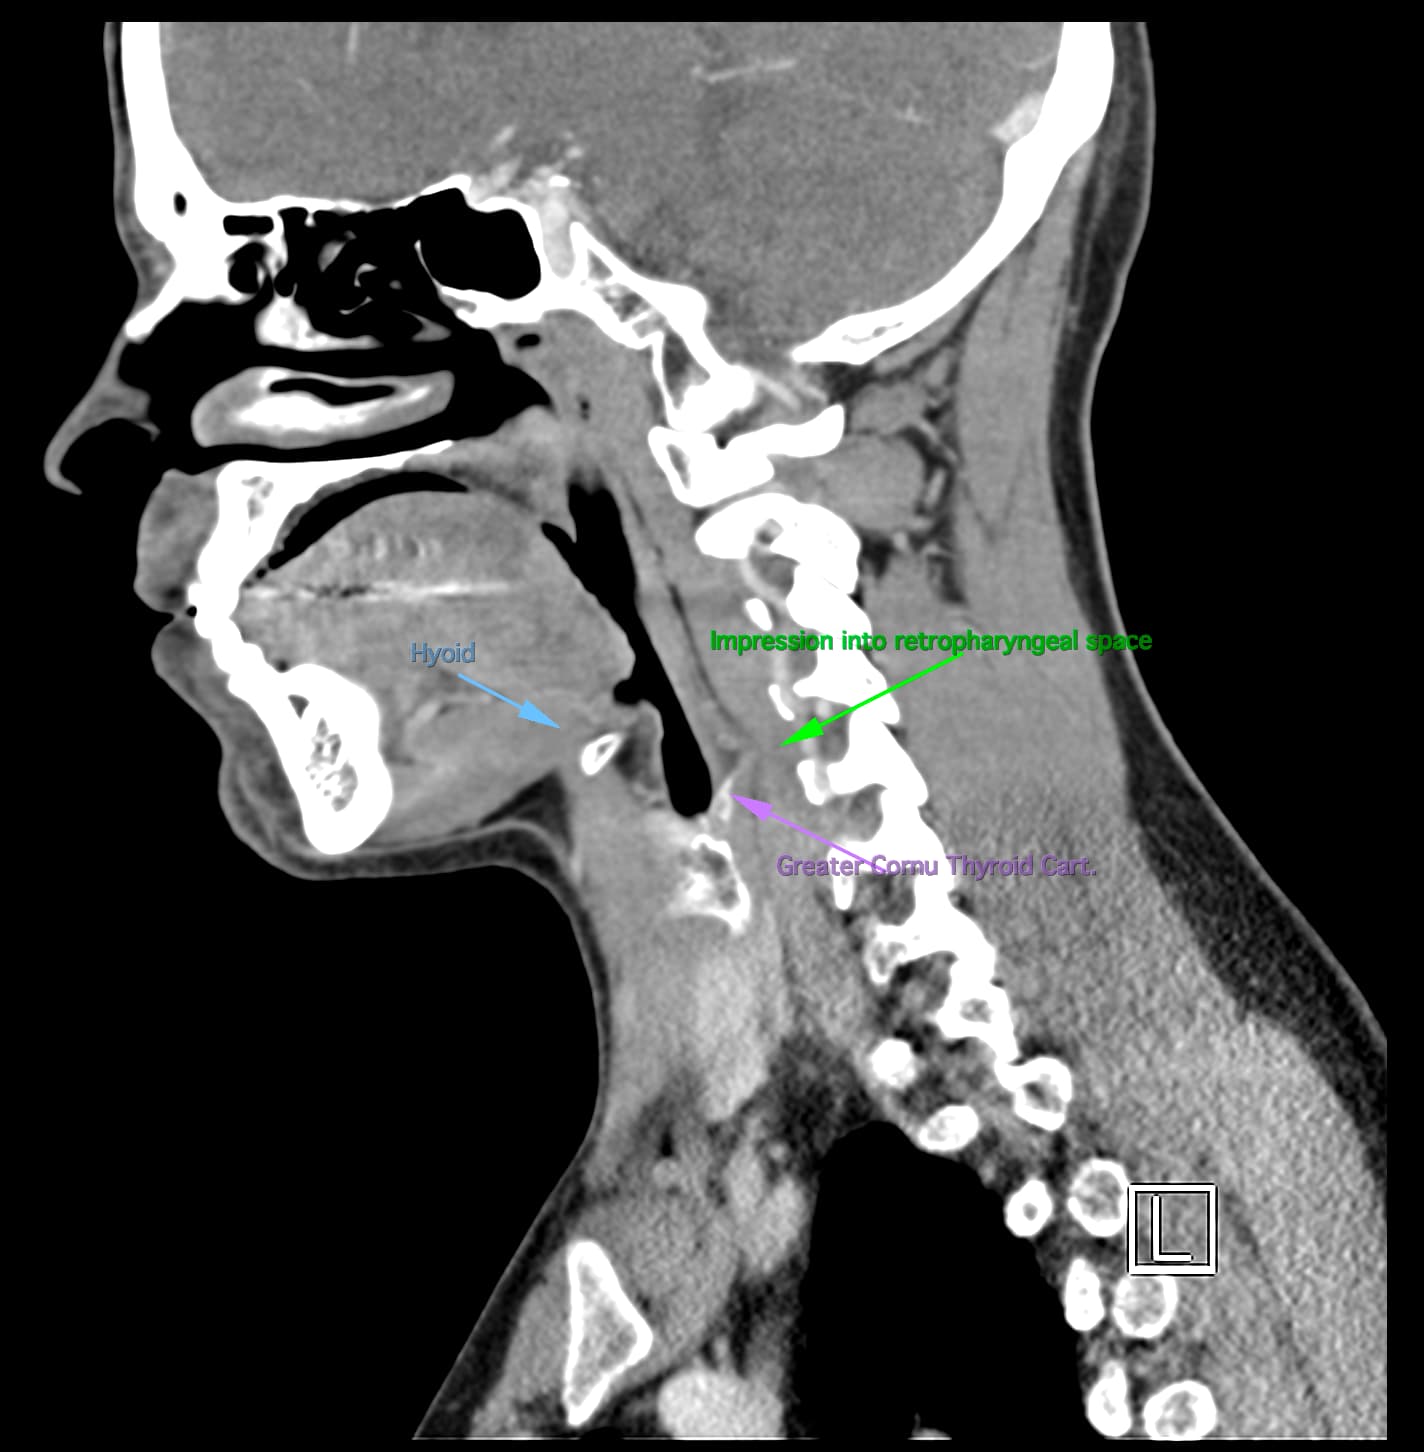

So, 2 years ago was the first time I came across Living with Eagle, filled with descriptions of all my symptoms, and a slew of scans showing very obvious bone chunks in the neck. Since I studied bio in college, and these bones are obvious, I figured I’d take a stab at looking at my own past scans and, low and behold, mild–but present–ossification of my stylohyoid ligament. Perhaps more relevant in my case, in the process of learning enough of the anatomy to understand axial images I noticed another weird thing–my right external carotid artery is in the wrong place. Instead of sitting lateral to my hyoid greater cornu, it’s medial. Hmm.

Tonsil surgery did solve the problem of my tonsils hurting, because they were gone, but no resolution of other symptoms. This was a year ago. I’ve been to PT, SLP, and now back to PT while I trial gabapentin for the neurologist. PT#2 discovered a bunch of significant atrophy in my upper right shoulder/back, and, you guessed it it’s all right sided. I’ve since then, thanks to radiopedia and Netter’s, also explored my images and noticed a few other anomalies in my scans, including an extended right thyroid superior cornu which appears to be pressing strongly into my neck also in the general area of pain, and an occipital artery branching off and wrapping around the internal carotid. Frustratingly these also weren’t mentioned on rads reports. My swallow study by the SLP showed obvious asymmetry with my swallow, but the SLP reported it symmetric and radiology apparently doesnt read the A/P view in their modified barium swallow studies? This is not inspiring faith in the academic institution I attended, but what can I possibly know they dont?

I’m here cause I’ve learned so much, and ya’ll seem to be the internet experts of weird head/neck issues adjacent to the stylohyoid chain. The docs keep seeing me, and keep ordering imaging, and seem to not be talking to each other at all? Frankly it seems to me the answers are in already in the images… so I’ve included several, perhaps you’ll see something helpful and can offer a suggestion… I just know I’m exhausted, frustrated, in so much pain all the time I cannot function which is so demoralizing, and it’s getting worse despite physician recommendations.